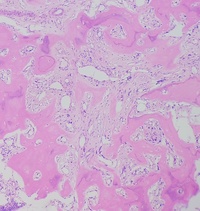

Primary myelofibrosis (PMF) with osteosclerotic progression 1

Author: Dr.Vikram Prabhakar

Category: Myeloid Neoplasms and acute leukemia (WHO 2016) > Myeloproliferative Neoplasms (MPN) > Primary Myelofibrosis (PMF)

Primary myelofibrosis (PMF) with osteosclerotic progression. Patient presented with pancytopenia and massive splenomegaly